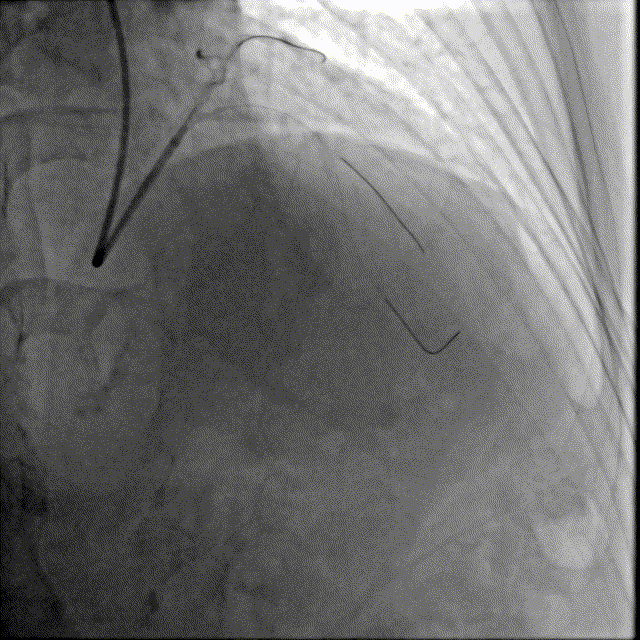

于前降支中段近段口串联2.5mm×18mm、3.0mm×18mm DES。

前降支开口精确定位植入3.5mm×18mm DES。

2.5mm-3.5mm后扩球囊后扩张。

最终结果满意,复查IVUS支架膨胀、贴壁良好!